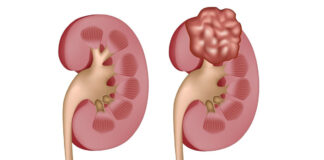

Η χορήγηση ανοσοθεραπείας μετά τη νεφρεκτομή αυξάνει την επιβίωση σε ασθενείς...

Ο καρκίνος του νεφρού αποτελεί ένα από τα δέκα συχνότερα νεοπλάσματα σε άντρες και γυναίκες. Τα επιδημιολογικά δεδομένα μάλιστα δείχνουν ότι η διάγνωση αυτής...